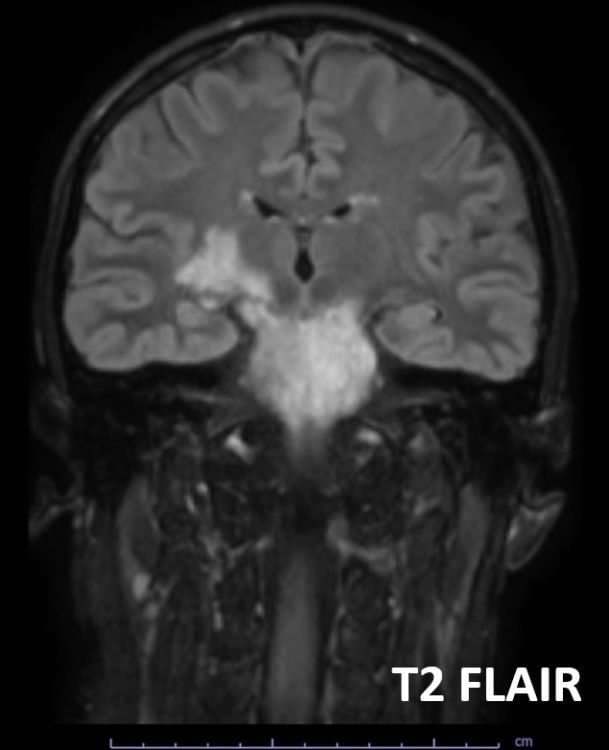

Intracranial HYPOtension, imaging findings and diagnostic approach Imaging and learning points in 🧵 🧠 #Neurology #neurosurgery #MedEd #radres #futureradres #neurorad American Society of Spine Radiology (ASSR)